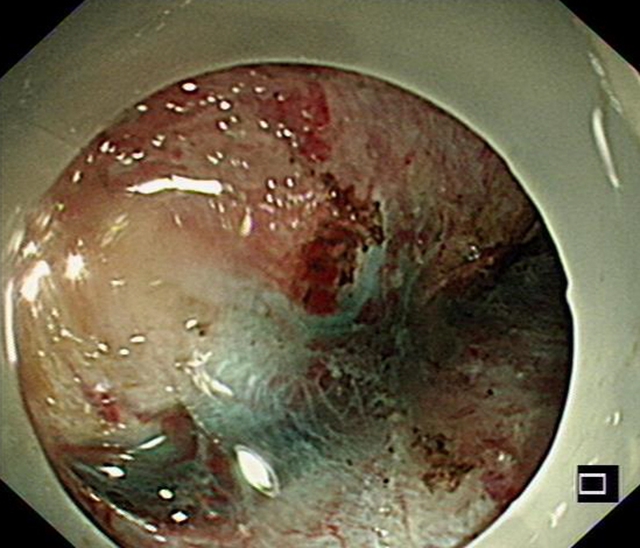

胃内大型黏膜下肿物破溃出现,箭头处为溃疡处

今年春节前夕,72岁的李婆婆被送入西南医科大学附属医院急诊科就诊时,呈休克状态,伴有呕血、黑便与贫血等症状。胃镜检查发现,她是因胃黏膜下肿物破溃出血才导致出现系列症状。

“切掉肿物,出血就会停止。”西南医科大学附属医院消化内科副主任汤小伟副教授介绍,李婆婆体内胃肿物直径约4厘米,邻近肝脏、胰腺等重要脏器。这类肿物常隐藏于黏膜之下,早期没有明显症状,倘若未能及时发现,就会悄悄增大导致疼痛、出血、梗阻,甚至危及生命。